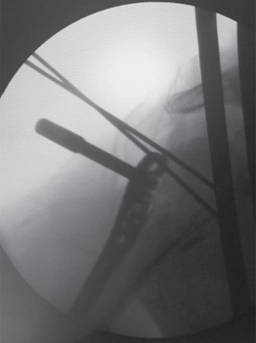

Bajo anestesia general, el paciente en decúbito supino en posición de silla de playa se inicia abordaje lateral acromial sin sobrepasar 5 cm de la punta del acromion, se diseca entre el deltoides anterior y medio, se hace disección y exposición de la cabeza humeral. Posteriormente se realiza fijación de manera percutánea con un clavo de Kirschner y se procede, bajo revisión fluoroscópica, a visualizar reducción de fractura de la metáfisis y tuberosidades (Figura 1). Se coloca placa sobre la piel ejerciendo una presión de impronta para determinar longitud y se realiza incisión distal (Figura 2). Teniendo en cuenta previa palpación y disección del nervio axilar, se desliza la placa (Figura 3) y se fija proximalmente con 3 tornillos autobloqueados en la cabeza (los tornillos más distales del implante en la posición A y B ), en algunas ocasiones se usan los tornillos de la posición C y se revisa bajo fluoroscopio reducción y posición de los tornillos y posteriormente con tornillo de cortical se adosa placa al hueso para luego colocar tornillos corticales o de bloqueo diafisarios y el tornillo de bloqueo distal (Figura 4).

Figura 1: Fijación transitoria de la fractura con agujas de Kirschner y colocación de clavo para medir altura de la placa.